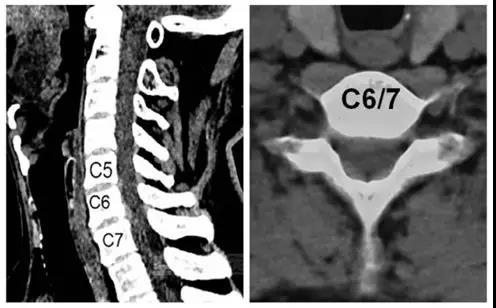

术前CT

术前核磁

诊断:颈椎病(C6/7)